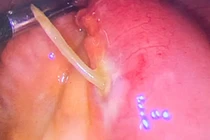

Các bác sĩ Bệnh viện Hữu nghị Việt Nam - Cuba Đồng Hới đã phối kết hợp, thực hiện thành công nội soi phế quản cấp cứu lấy dị vật dưới gây mê cho bệnh nhân 9 tuổi.